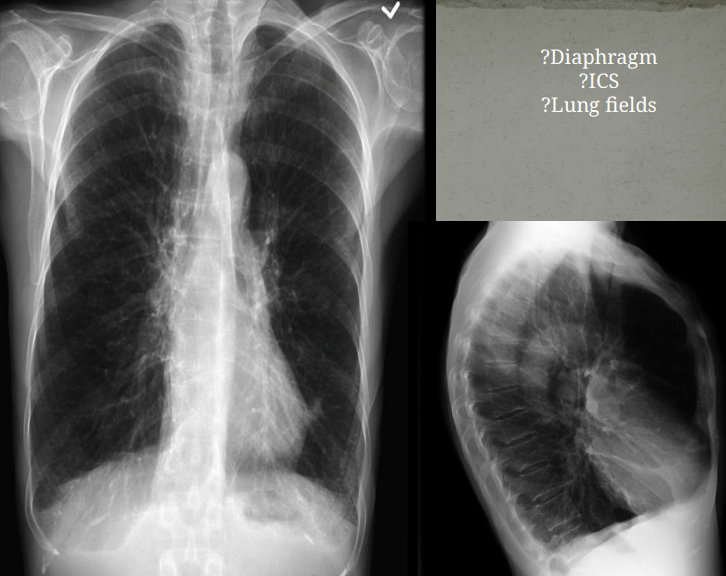

What view

PA (lower diapjragm, full lungs/large, horizontally oriented clavicales, scapula not displaced)

AP (higher diapjragm, smaller lungs, obliquely oriented clavicales, scapula displaced, falsely enlarged heart and medastinum)

COPD patient

diaphragm flat

barrel chest on lateral view (AP diameter increase)

widened intercostal spaces

lungs hypper enflated→globular heart